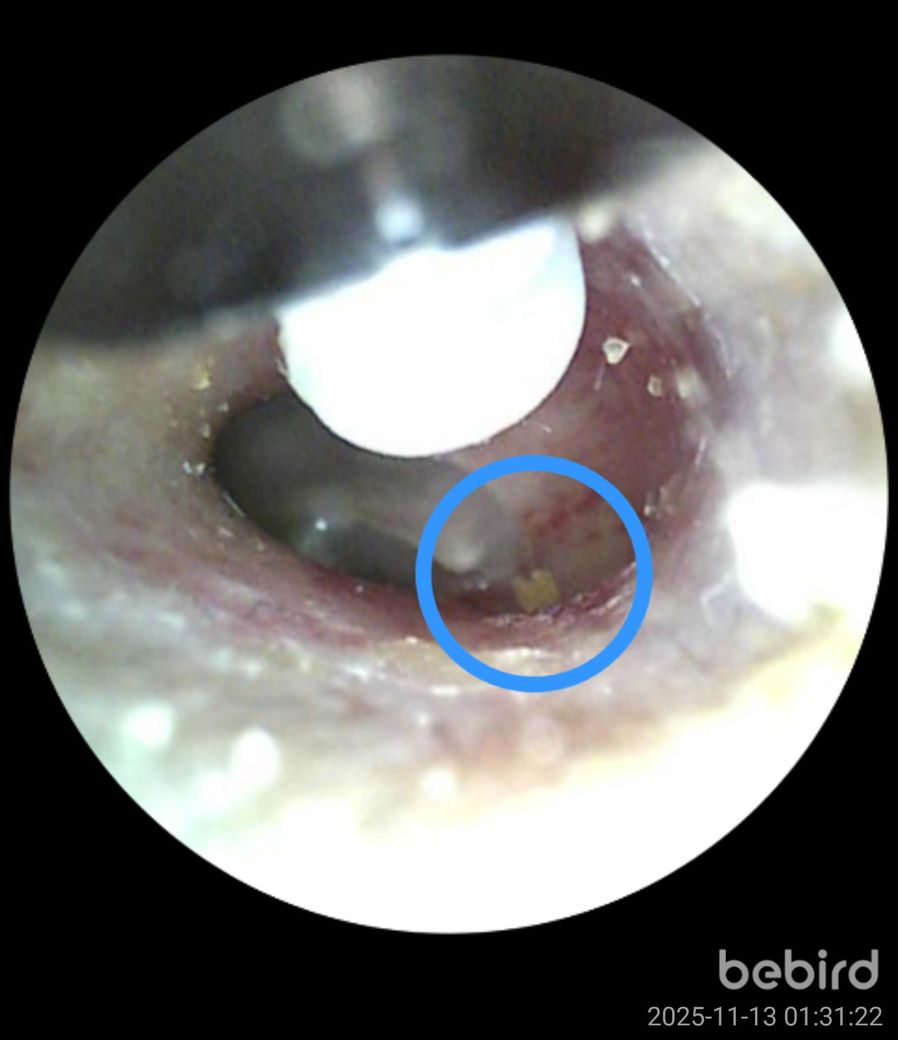

비버드를 가지고 주기적으로 귀를 확인하는 편입니다. 그런데 몇일째 고막근처에서 귀지처럼 보이는게 움직이지 않고 있는걸 확인했습니다. 처음 봤을때는 놔두면 나오겠지 싶어서 놔뒀는데 가만히 있는거보면 이물질인가 싶기도 합니다. 이거 귀지가 맞을까요?

• 1번 째 사진